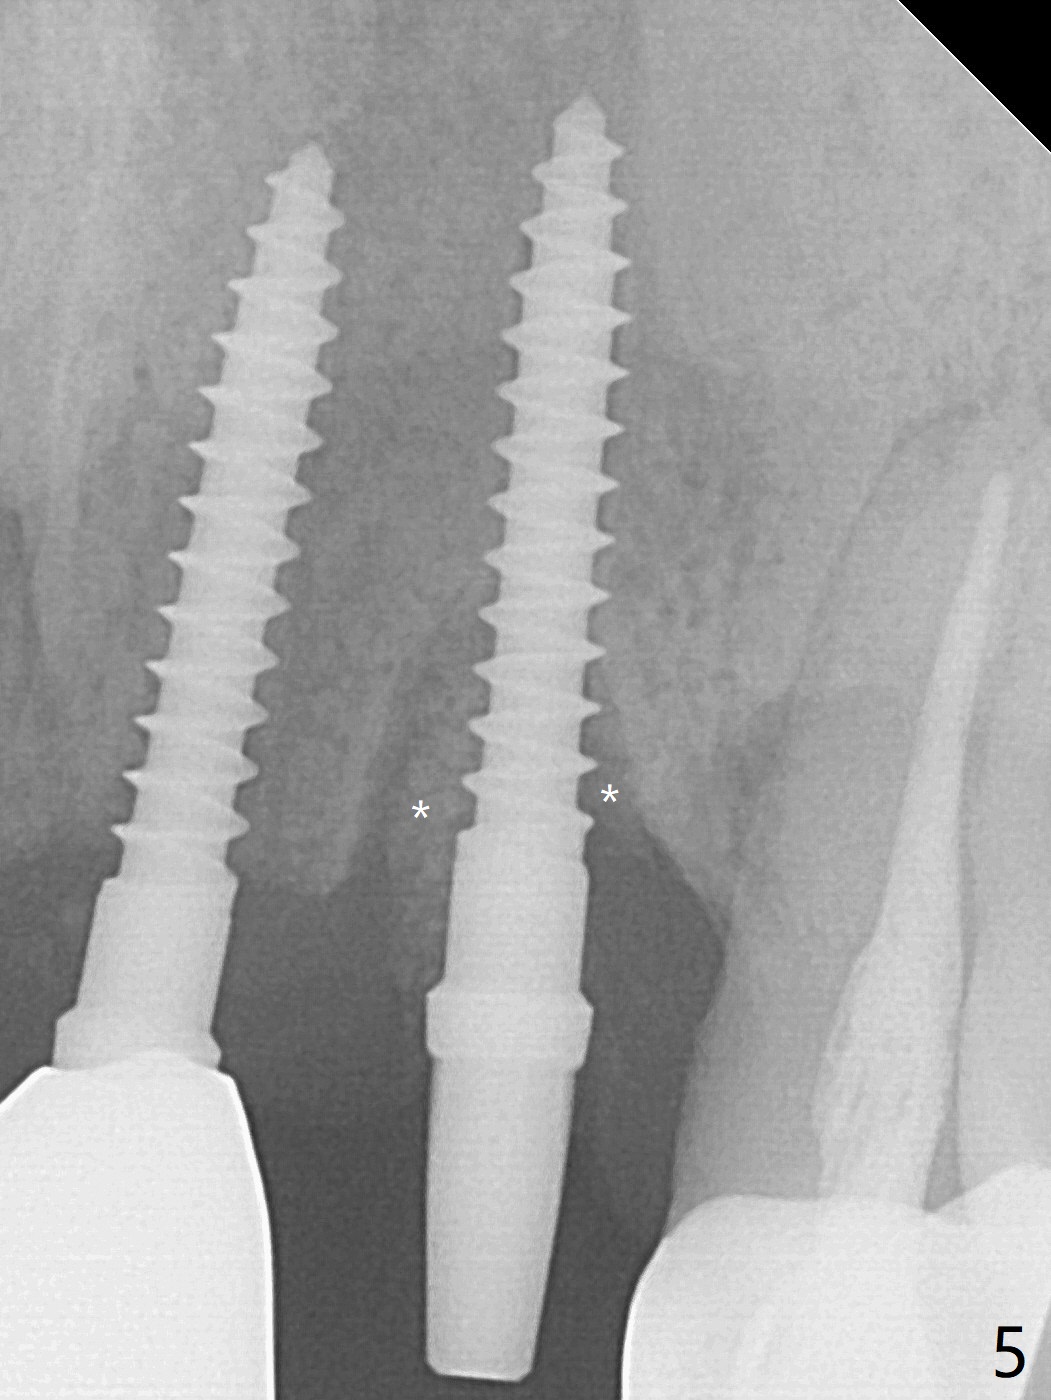

The tooth #10 has severe gingival recession (Fig.1) with loss of the buccal plate (Fig.2 *). After the initial osteotomy depth (Fig.3) increases by 2 mm, a 2.5x14(2) mm 1-piece implant is placed with insertion torque >60 Ncm (Fig.4). Palpation indicates the native bone apparently wider than CT shows. There is no sign of buccal or palatal plate perforation by palpation during osteotomy or implant placement. Vera Graft is placed repeatedly around the coronal threads (Fig.5-7 *). An immediate provisional is fabricated to close the socket (Fig.8). The buccal plate appears to collapse 1 month postop (cortical plate graft apparently more appropriate in this case); the margin of the provisional is trimmed so that the gingiva may grow incisally (Fig.9). The provisional dislodges several times postop due to short abutment. By nearly 4 months postop, the coronal bony defect seems to have been repaired (Fig.10 *). The tooth #11 has tenderness with bone loss (Fig.10 ^), corroborated by CT (distal bone loss, Fig.11 *). Since the apical bone is narrow (Fig.12), a narrow long implant is expected (Fig.13). Use an implant (3.5x13 mm) consistent with those at #14 and 15.